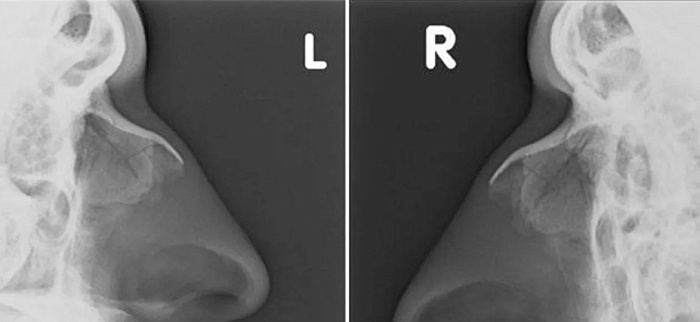

Рентгенография костей носа – важный метод прицельного исследования для оценки состояния костей носа.

Диагностическая услуга выполняется в одной проекции.

• травма лицевой области и носа;

• для исключения перелома костей носа;